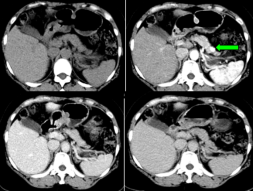

4胆管癌CT/MRI影像表现肝门胆管癌:多可在肝门区发现软组织结节或肿块,肝内胆管扩张中段和下段胆管癌:肝内和近段胆管扩张明显,胆管扩张突然变小或中断,局部胆管壁增厚或可见软组织结节或肿块,增强扫描明显不均匀强化

胆道梗阻病因诊断分析良性:胆管扩张程度较轻,呈枯枝状或残根状;扩张的肝外胆管逐渐变细;扩张的胆管远端可见结石影,出现半月征靶征。恶性:胆管扩张程度较重,呈软藤状;扩张的胆管突然中断,又未见结石影;梗阻端出现软组织块影,胆管不规则狭窄;肝门部梗阻多为恶性;胰头部同时显示扩张的胆管和胰管,出现所谓双管征